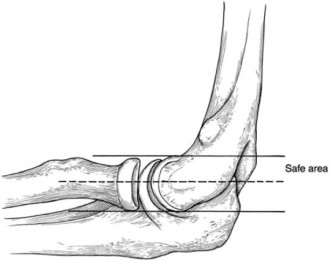

Preoperative Planning and the "Danger Zone"

The surgical management of VEO involves arthroscopic debridement and posteromedial osteophyte excision. However, the decision-making process is fraught with biomechanical peril. The surgeon must navigate the delicate balance between relieving impingement and maintaining medial column stability.

The posteromedial olecranon serves as a secondary bony stabilizer to valgus stress. If the surgeon resects too much of the olecranon—specifically violating the native medial cortex—the primary restraint (the UCL) is subjected to exponentially higher tensile forces. This over-resection pushes the elbow into the "danger zone," frequently resulting in iatrogenic valgus instability that subsequently requires a Tommy John surgery (UCL reconstruction). Preoperative templating dictates that resection should be limited strictly to the reactive osteophyte, typically no more than 2 to 3 millimeters of bone.